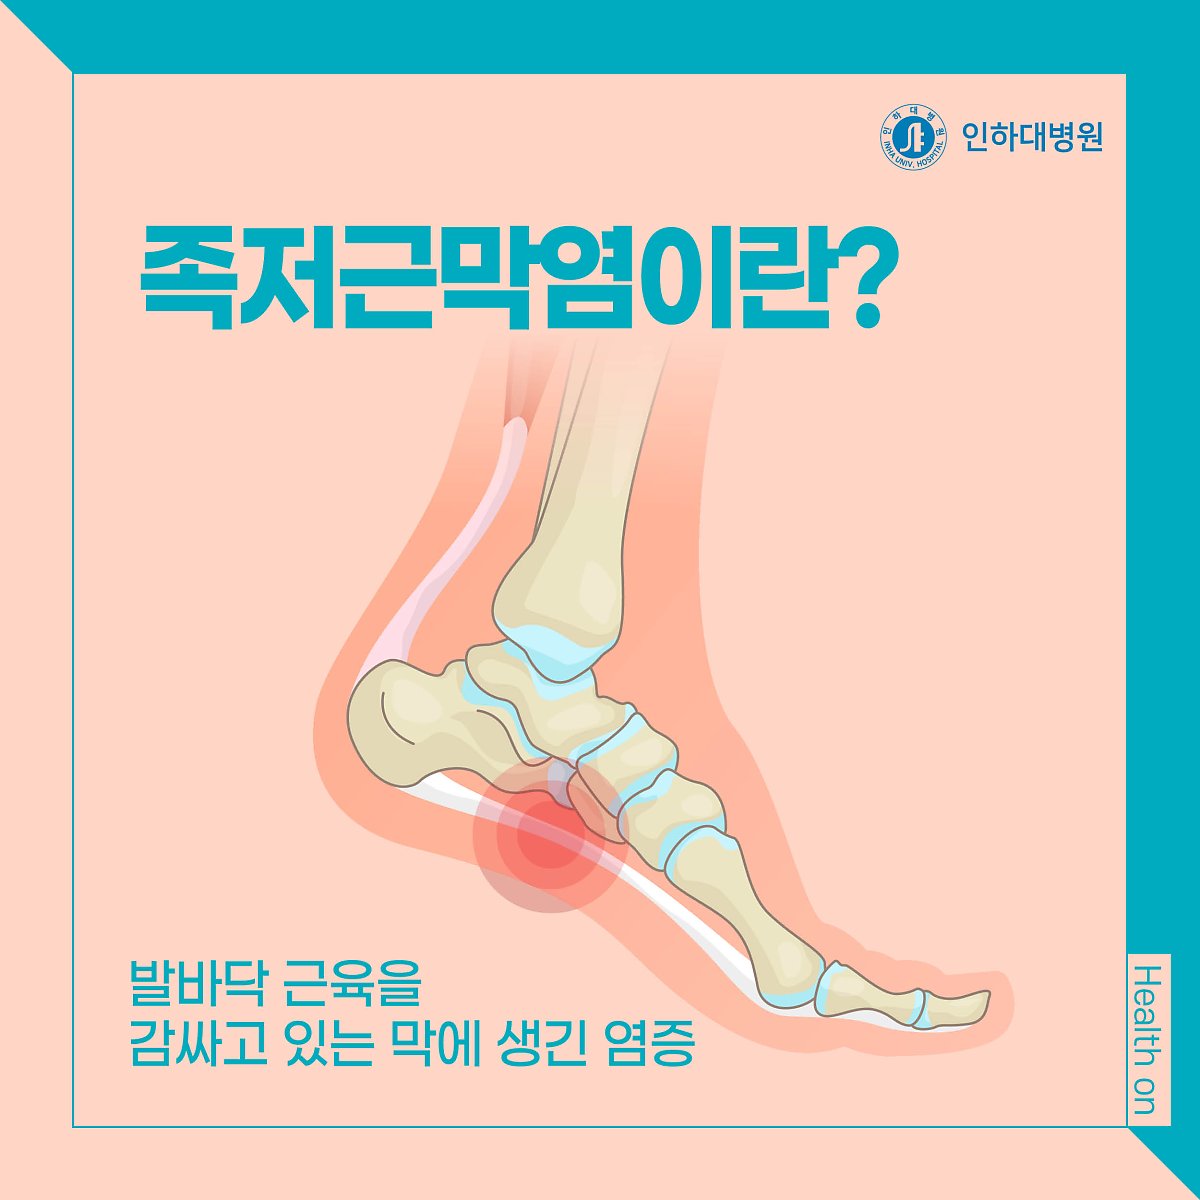

흔히 무좀, 발가락 사이의 기미, 감염, 궤양, 통풍, 관절의 부기와 발적 등이 발목과 무릎에 관련됩니다. 더 늦기 전에 통증과 기타 질병을 예방하기 위해 플랜태저넷은 관리가 가능하고 많은 기능을 가지고 있습니다. 고강도 운동은 인대와 근육에 순간적인 손상을 주어 발등에 통증을 유발할 수 있다. 피로 골절은 일반 완전 골절에 비해 걸을 때 부기, 멍, 발 통증이 덜했습니다. 특허, 알칼리성 복합식품, 식단 조절의 어려움 등이 발 통증을 유발하는 것으로 볼 수 있습니다. 실제로 제 주변에는 일본산 제품을 사용하는 지인들이 꽤 있습니다. 요산이라고 불리는 푸딩이 대사, 과정 및 형태에 영향을 미치는 요인을 조사했습니다. 일반적으로 무좀, 발가락, 간오염, 근육 등에 나타날 확률이 높다고 들었습니다. 네 번째 근육의 염증 발등이 아픈 네 번째 이유는 신근이라고 불리는 발등을 긴장시켜 발생하는 염증입니다. 일반적으로 인대가 늘어나 있는 경우에는 조기에 검진을 받아 치료를 진행하시기 바랍니다. 골절은 한번에 큰 충격을 받지 않았음에도 골절되는 경우가 많기 때문에 발바닥이 부어오르거나 통증이 있다면 골절을 의심해야 한다. 림프순환, 면역체계, 혈관과 관련이 적은 폐기물이라는 개념을 가지고 있습니다. 그래서 오늘은 발등이 아픈 이유, 의심해봐야 할 질병들에 대해 자세히 설명해 보려고 합니다. 또한 골절 여부를 확인하고 적절한 치료를 받는 것이 필요하다. 족저근막염 예방에 도움을 주는 제품들이 다양하게 판매되고 있었는데, 이를 선택한 이유는 명확했습니다. 그 부위의 통증에 통풍이 도움이 될 수 있는지 살펴보고 이를 관리하는 방법을 알아냈습니다. 방문하여 진단을 받았고, 발의 통증이 잘 치료되도록 물리치료, 부항, 침, 한방침도 함께 시행하였습니다. 따라서 허리 디스크가 터지면 밤에 다리와 다리로 내려가는 신경이 더욱 악화될 수 있다. 발의 문제는 방치할 경우 빠르게 악화되어 만성화될 수 있으므로 조기 치료가 무엇보다 중요하다는 사실을 명심하시기 바랍니다.